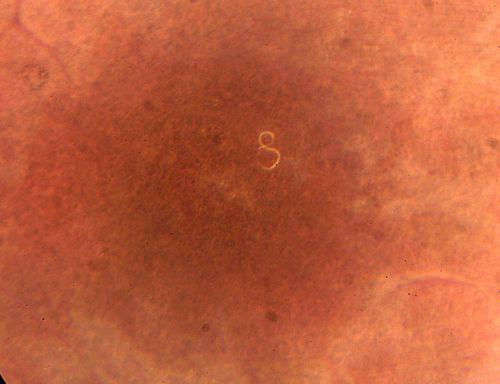

DUSN - Diffuse Unilateral Subacute Neuroretinitis - Nematode

nematode21.jpg